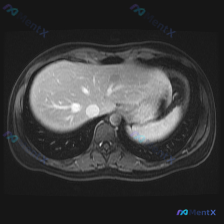

用户最初的关注点是「脾脏病变」,但拿到的是一幅腹部MRI T1加权轴位图像。

- 脾脏:位于左上腹,形态、大小及T1信号均未见明显异常——这是首先要明确的,直接推翻了预设的“脾脏病变”方向。

- 肝脏:这是真正的异常所在。肝轮廓尚可,实质内可见多个类圆形高信号灶(T1亮白色),边缘清晰锐利,其中一个位于肝右叶近肝静脉/下腔静脉汇合处,信号显著。

- 其他:肝静脉、下腔静脉走行正常,无受压移位;腹膜后、脊柱及背部软组织未见明确异常。

这个病例的核心影像特征是「肝脏多发T1高信号灶」。在T1WI上出现高信号,特异性很强,通常提示三种成分:脂肪、亚急性出血(正铁血红蛋白)或高浓度蛋白质。

结合病灶“边界清晰、形态规则”的特点,第一印象倾向于良性病变,但绝不能直接排除恶性(比如某些伴有出血或富含脂质的转移瘤)。